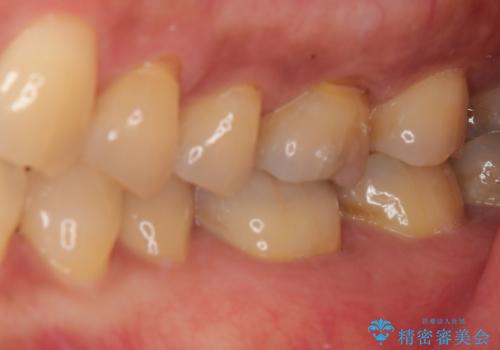

ゴールドインレーは銀歯のインレーやセラミックインレーと比べ、「技工操作の精度が高く、適合が著しく良い」というメリットがあります。特に「適合の良さ」は再治療のリスクを防ぐ上でとても重要な要素となります。

咬み心地はとても良好で、全く違和感がなく、患者様には大変満足していただきました。